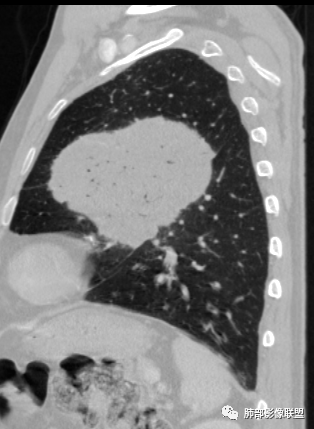

左肺上叶大肿块,膨胀性生长,边界清,密度较低,见部分坏死区,强化弱,肿块见支气管充气V扩张征,分布僵直,枯树枝特点,另一个重要特点血管造影征,淋巴瘤,肿块长轴与胸膜平行,与隐球菌鉴别,隐球荚膜抗原检查,明确诊断经皮肺穿刺。另胸膜钙化(问诊既往有无患胸膜炎病史)。

左肺上叶胸膜下肿块,膨胀性生长,边界清晰,密度不均部分坏死,未见强化,病灶内支气管迂曲扩张,病灶长轴与胸膜平行,胸膜下脂肪间隙存在,胸膜钙化,考虑放线菌?毛霉?鉴别淋巴瘤

左肺上叶肿块,宽基底与胸膜相连,跨叶裂,边缘清晰膨隆,可见小分叶,其内支气管充气,部分扩张、僵直,呈枯枝征,支气管达边征,增强无明显强化,可见血管造影征,考虑恶性病变,淋巴瘤,鉴别粘液腺癌。

糖尿病史,慢性病程,左肺巨大肿块,跨叶生长,肿块近端可见充气支气管征及悬浮气泡,轻度圴匀强化,病变长轴与胸膜平行,炎性标志物正常,考虑放线菌,其次淋巴瘤

我再建一下血管。支气管进入,但是近端推移,堵塞

近端支气管堵塞、推移为主

内部支气管扩张

大肿块、表面光滑但深分叶,肺门侧支气管堵塞

回头看,内部支气管近端其实不连续,伴随肺动脉不存在

这两点就不符合